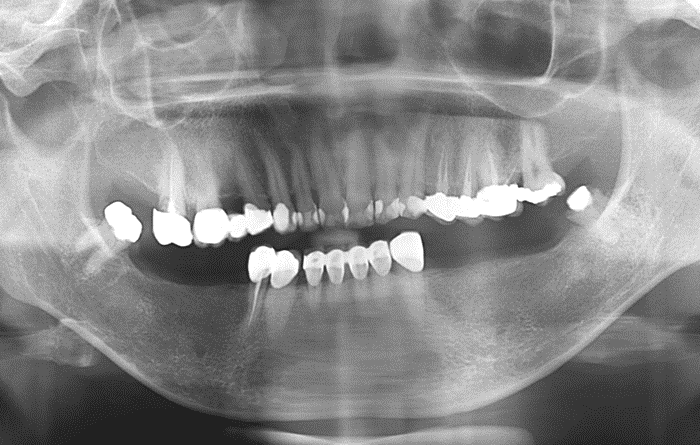

뼈이식을 필요로 하지 않는 단순 임플란트는 간단한 술식으로만 생각하는 환자분들도 계십니다.

그러나 임플란트를 장기간 성공적으로 사용하시기 위해서는 수술 전 정밀한 분석을 통해 3차원적으로 정확한 위치에 임플란트를 심고

환자 개인에게 최적화된 보철 치료를 진행해야만 합니다. -

임플란트 수술-보철에 대한 많은 지식과 경험을 보유한 구강외과 전문의 원장이 단순 임플란트도 직접 처음부터 끝까지 진료를 진행합니다.